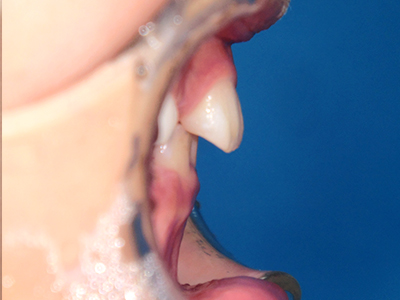

歯並びの相談に来られるお子様は、口呼吸をしているケースが多く、これが歯並びに大きな影響を与えています。

- 口呼吸をしている

↓ - 舌の位置が悪くなる

↓ - 頬の圧力が上の歯列にかかりやすくなる

↓ - 上あごが狭くなる

↓ - 下あごが狭くなる・下あごの位置が悪くなる

↓ - さまざまな不正咬合が生じる

ないき歯科クリニックでは、上あごの成長不足を補い、鼻呼吸を獲得しつつ歯列を整え、将来のお口をより健康な状態にすることをゴールに定める矯正治療をおこなっています。